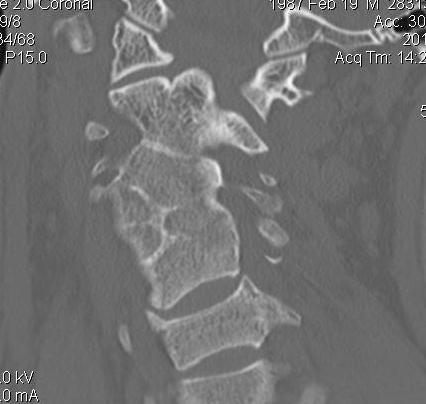

CT scan

Body fusion / block vertebrae

Hemivertebrae

Flattening & widening bodies

Hypoplasic discs

Cervical spina bifida